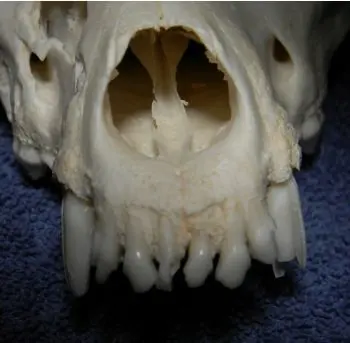

MANDIBULAR CANINES

These teeth make up the majority of the mandibular cross-sectional area. There is actually more tooth than bone in the area of the mandibular canines. If excessive force is used to extract a solid lower canine tooth, severe separation of the mandibular symphysis or mandibular fracture may result. Additionally, the middle mental foramina and the associated neurovascular bundles are located on lateral surface of the mandible near the apex of the roots of the lower canine teeth. Damage to the bundle may cause significant hemorrhage or permanent loss of sensation of the lower lip.